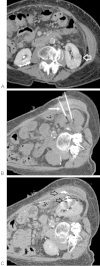

Although percutaneous ablation of small renal masses is generally safe, interventional radiologists should be aware of the various complications that may arise from the procedure. Renal hemorrhage is the most common significant complication. Additional less common but serious complications include injury to or stenosis of the ureter or ureteropelvic junction, infection/abscess, sensory or motor nerve injury, pneumothorax, needle tract seeding, and skin burn. Most complications may be treated conservatively or with minimal therapy. Several techniques are available to minimize the risk of these complications, and patients should be appropriately monitored for early detection of complications. In the event of a serious complication, prompt treatment should be provided. This article reviews the most common and most important complications associated with percutaneous ablation of small renal masses.